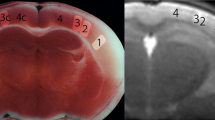

Computed tomography cannot detect pure cytotoxic edema (shrinkage of extracellular space and oncotic cell swelling without net water uptake), because cytotoxic edema does not affect X-ray attenuation or induce tissue swelling (Fig. 1). It is evident that cytotoxic edema is associated with impairment of proton diffusion detected by diffusion-weighted MRI (DWI) and measured on apparent diffusion coefficient (ADC) maps. A decrease in ADC 90 min after MCA occlusion was associated with extracellular fluid loss, swelling of various cellular compartments, and neuronal shrinkage [33]. Apparent diffusion coefficient declines immediately when CBF falls below 20 to 40 ml/100 g × min in animals and humans [34, 35] corresponding well with the CBF threshold for the shrinkage of extracellular space [28]. High-signal lesions on DWI representing cytotoxic edema can disappear with reperfusion, but are closely associated with infarction if persistent as shown in animal and clinical studies [36,37,38]. Detecting cytotoxic edema at the time of stroke symptom onset immediately after arterial occlusion with high sensitivity, DWI identifies brain regions suffering from CBF below 40 ml/100 g × min and, thus, tissue regions that may not survive without blood flow restoration. In patients with persistent MCA occlusion, a DWI lesion >145 cm3 detected within 14 h of stroke onset is accurately predictive for the development of life-threatening (malignant) MCA infarction [39]. Diffusion-weighted MRI does not, however, specifically identify brain tissue being prone to die even with reperfusion.

Embolic pattern of cytotoxic edema not detected by CT. a–d Four sections of cranial CT of a 62-year-old man 87 min after onset of left-sided hemiparesis. CT angiography (not presented) does not show arterial occlusion. Subtle small lesion in both cerebellar hemispheres not explaining the symptoms. e–h DWI at 3 h and 10 min after symptom onset shows an embolic pattern of small lesions in both cerebral and cerebellar hemispheres with predominance in the right central region explaining the stroke symptoms. The patient had a dissection of his aorta